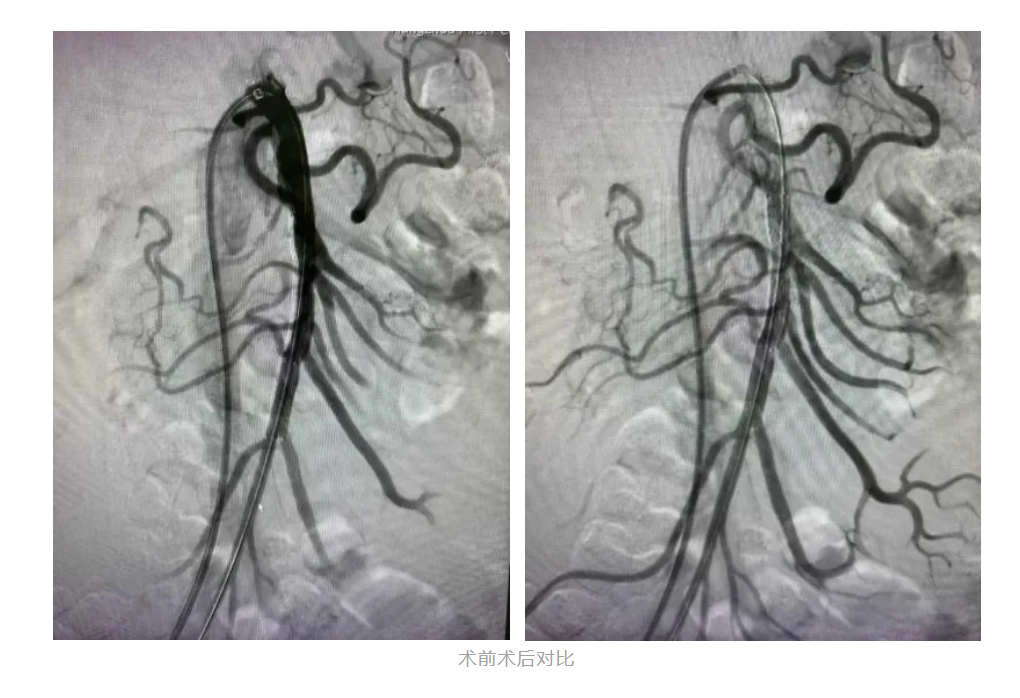

经过术前积极准备,团队共同努力为患者进行了肠系膜上动脉支架置入术。手术中,支架释放成功,假腔显影明显减少,肠系膜动脉真腔供血改善!